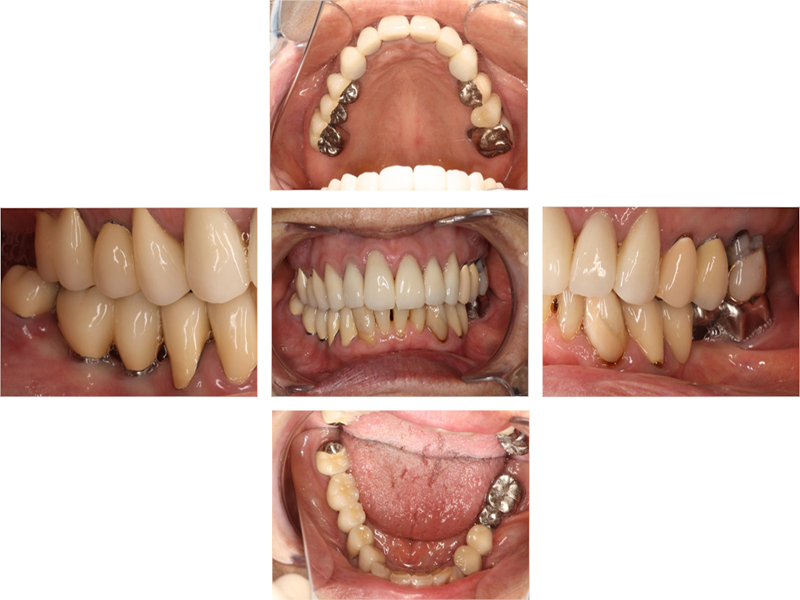

治療終了時

before

after